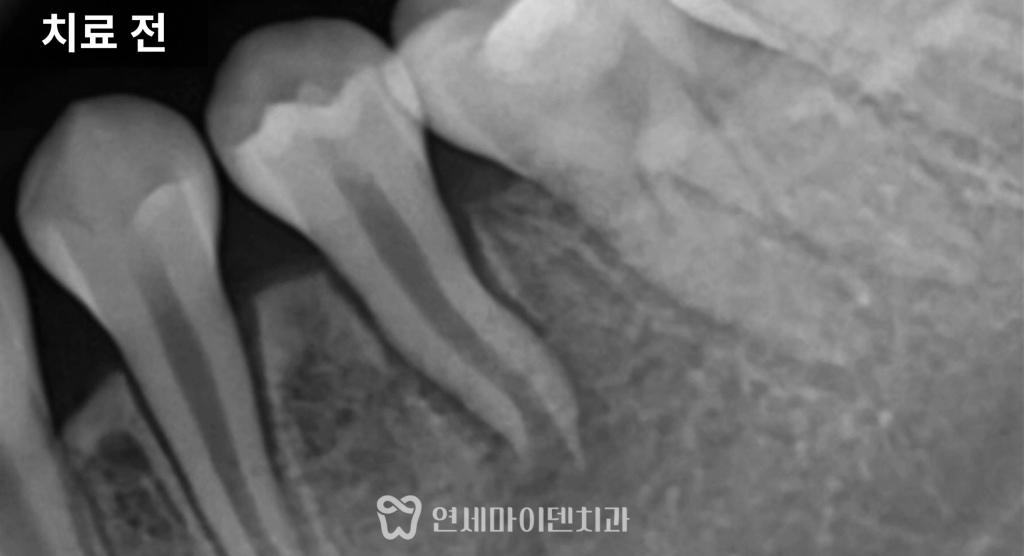

이번 케이스의 원인은

‘치외치(치아 안에 또 다른 치아 구조가 있는 경우)’였습니다.

치아 내부에 형성된 구조가

뿔처럼 돌출되어 있다가

어느 순간 부러지면서

신경이 구강 내로 노출되고

세균이 침투해 신경이 괴사된 상황이었습니다.